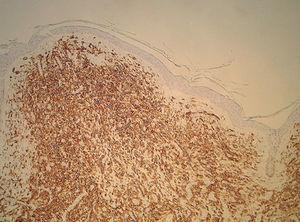

El paciente fue sometido a seguimiento con un completo estudio periódico, que ha incluido radiografías y gammagrafías óseas, pruebas de laboratorio, ecografía hepática, esplénica y biopsias cutáneas (todas fueron similares a la primera, con positividad para el azul de toluidina y el anticuerpo CD117, [fig. 2]). No se hallaron alteraciones significativas, hasta que en su última revisión detectamos una banda monoclonal IgG sérica, por lo que le fue practicado un aspirado y biopsia de médula ósea. El aspirado mostró una celularidad normal, pero en la biopsia aparecieron infiltrados multifocales densos, bien delimitados de mastocitos redondos típicos positivos para CD117, que constituye el patrón histológico más frecuente de afectación ósea en la mastocitosis sistémica3 (fig. 3). El nivel sérico de triptasa fue normal, 7,69 ng/ml (3-11 ng/ml).

Figura 2. Infiltrado de mastocitos en la dermis (tinción inmunohistoquímica con CD117, aumento original x100).